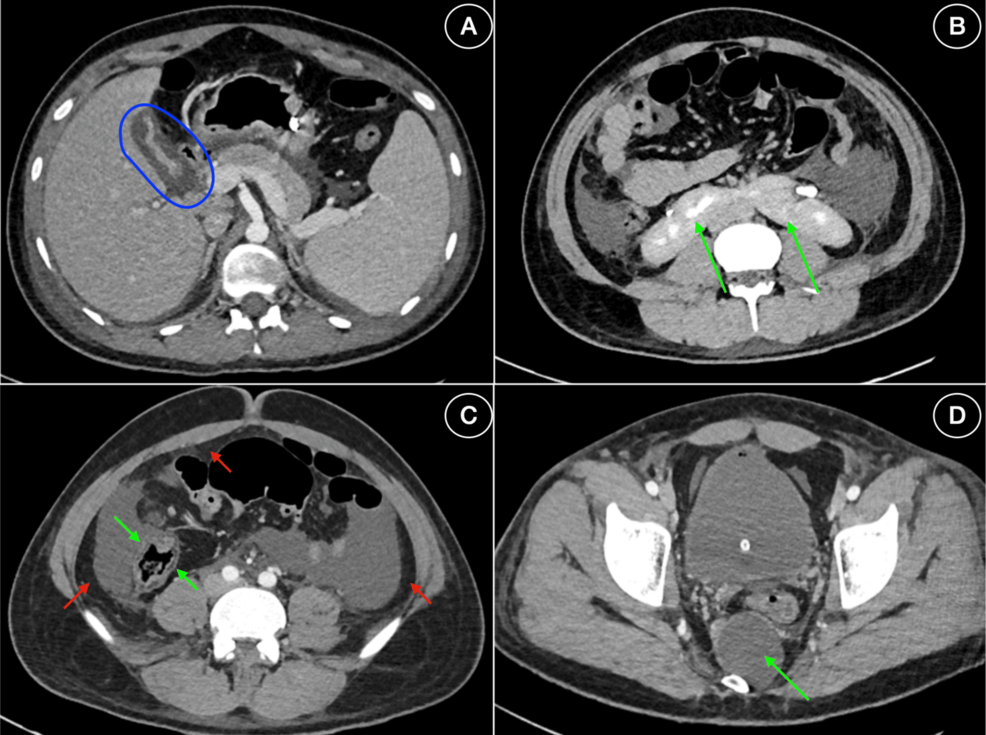

Concurrently, the patient’s abdominal pain intensified, shifting to the right upper quadrant. Despite the absence of gallstones on ultrasound (ruling out cholelithiasis), suspicion for cholecystitis arose due to Murphy’s sign and escalating pain. An abdominal CT scan confirmed acalculous cholecystitis – inflammation of the gallbladder without gallstones. This is a serious complication, often associated with critical illness and prolonged hospitalization. Hepatitis A-induced acalculous cholecystitis is believed to be related to inflammatory mediators and altered gallbladder motility.

* Imaging Studies:

* Chest X-ray: Small bilateral pleural effusions.

* Abdominal Ultrasound: No gallstones, but gallbladder wall thickening.

* Abdominal CT Scan: Confirmed acalculous cholecystitis with gallbladder edema and pericholecystic fluid.